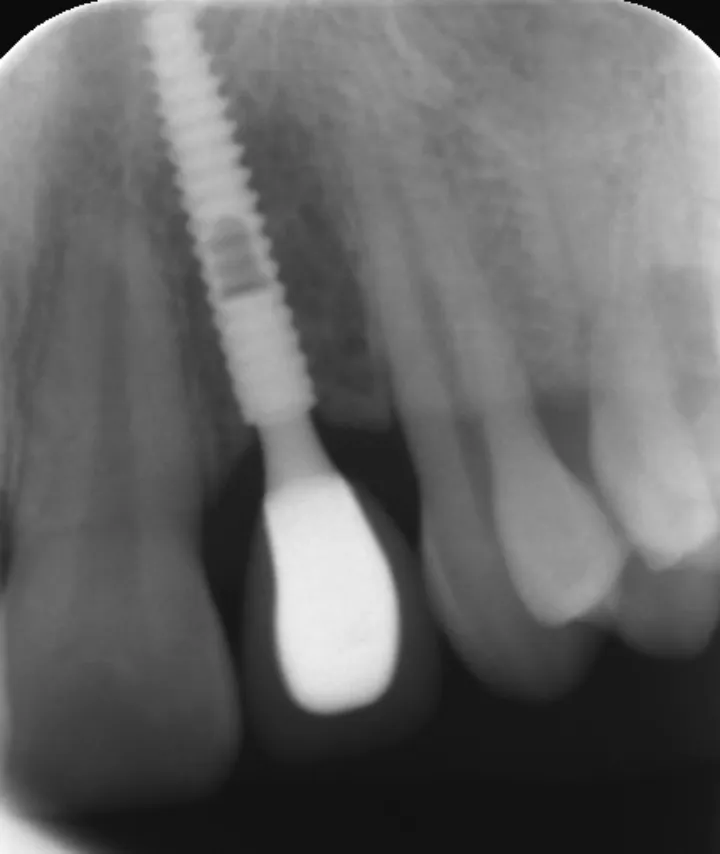

图 35 :术后 1 年随访 X 线影像。

3 号病例 - Patrick EXBRAYAT 医生(图 36 至 49)

女性患者,侧切牙 12 发育不全,长期使用临时修复手段。